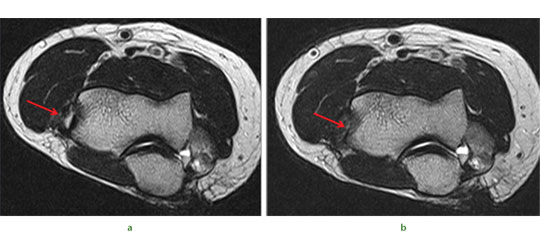

Some of our early results illustrate the potential benefits of this therapy. We treated a 43-year old woman who had sustained both a chondral injury and a symptomatic large posterior horn intra-substance tear of the medial meniscus (Fig.5a). Intra-operatively her meniscus was found to be intact on the surface, and consequently we undertook needling of the posterior aspect of the medial meniscus to stimulate healing (Fig.5b). This was combined with treatment of the chondral lesion and subsequent injection of PBSC and HA. The patient was able to return to sporting activities by two years and at the time of review three years later, she was running three times per week. An MRI scan taken after three years demonstrates complete healing of the meniscal lesion (Fig.5d). A case report such as this does not provide irrefutable evidence that the meniscal healing was due to the PBSC, however, conventional wisdom tells us healing of such a lesion would not normally be expected after needling alone.

Fig. 5 A 43-year-old woman presented with a chondral injury of her left knee accompanied by symptomatic intra-substance tear of the medial meniscus.

Figure 5a – intra-operative view of the posterior aspect of the medial meniscus showing intact surfaces.

Figure 5b – arthroscopic view after multiple needling into the posterior aspect of the medial meniscus.

Figure 5c – pre-operative MRI scan showing intra-substance tear of the posterior aspect of the medial meniscus. Figure 5d – MRI scan after three years showing complete healing of the meniscal tear.